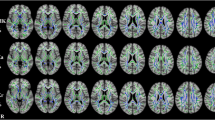

Mean kurtosis (MK), axial kurtosis (AK), radial kurtosis (RK), kurtosis fractional anisotropy (KFA), and the mean relative quantitative susceptibility mapping (mrQSM) values in the U-fiber region were compared between 49 pwRRMS and 48 healthy controls (HCs). The U-fiber were divided into upper and deeper groups based on the location. The whole brain volume, gray and white matter volume, and cortical thickness were obtained. The correlations between the mrQSM values, DKI-derived metrics in the U-fiber region and clinical scale scores, brain morphologic parameters were further investigated.

The decreased MK, AK, RK, KFA, and increased mrQSM values in U-fiber lesions (p < 0.001, FDR corrected), decreased RK, KFA, and increased mrQSM values in U-fiber non-lesions (p = 0.034, p < 0.001, p < 0.001, FDR corrected) were found in pwRRMS. There were differences in DKI-derived metrics and susceptibility values between the upper U-fiber region and the deeper one for U-fiber non-lesion areas of pwRRMS and HCs (p < 0.05), but not for U-fiber lesions in DKI-derived metrics. The DKI-derived metrics and susceptibility values were widely related with cognitive tests and brain atrophy.